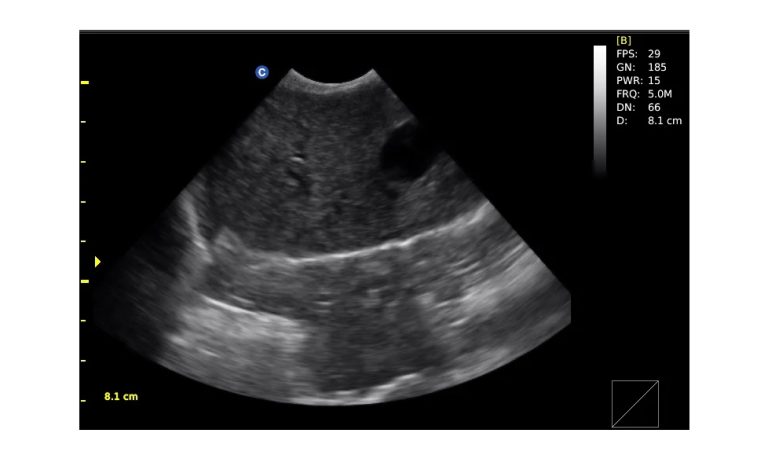

Ultrasound

Wide range of Ultrasound machines that suites a variety of applications from abdominal to rectal scans, we take in consideration how the world is moving towards mobility and mobile applications.

SonoScape Pro Pet E11

Smart Imaging

Introducing the first portable ultrasound with the C-Field+TM platform, redefining diagnostic imaging. Designed for veterinarians, it delivers unmatched clarity, ultra-fast processing, and seamless adaptability for all species. Experience Smart Imaging, Heartfelt Care—anywhere.

Equipped with cutting-edge veterinary software and optimized workflows, it embodies our commitment to Smart Imaging, Heartfelt Care – Wherever Their Journey Leads, with unparalleled performance and adaptability, this innovative system empowers veterinarians to provide exceptional care across all diagnostic applications,

Esaote MyLab Sigma; So Fast, So Easy

Esaote’s new MyLab™SigmaVET is the smart, portable solution that allows use of an ultrasound whenever a quick and complete diagnosis is required.